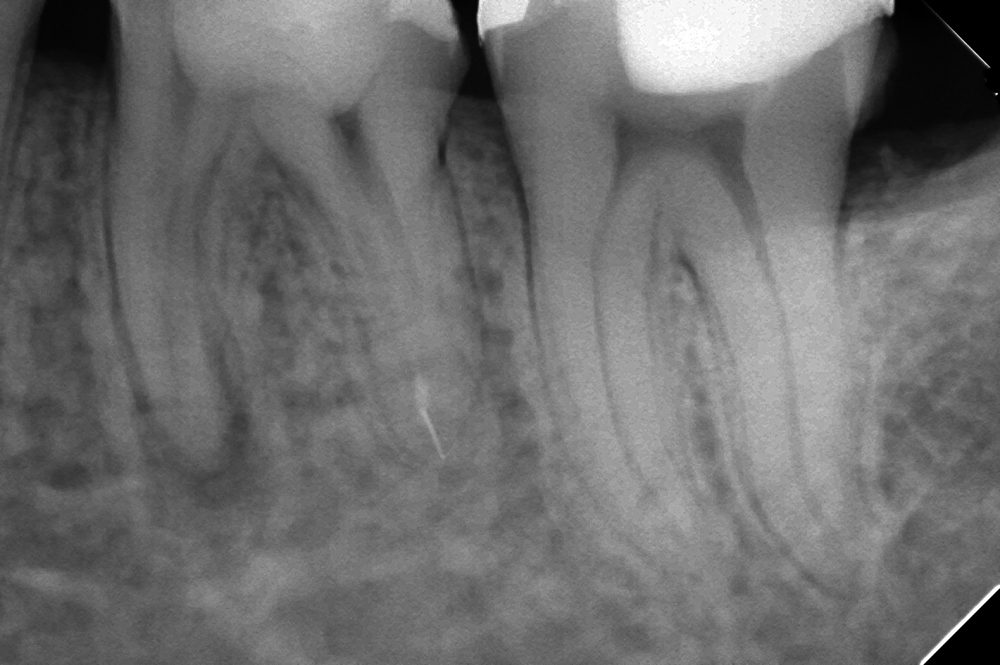

レントゲンで確認する限り、近心根に2本、遠心根に1本の破折した器具の残存が認められます。

除去を試みましたが遠心の1本がどうしても取れませんでした。